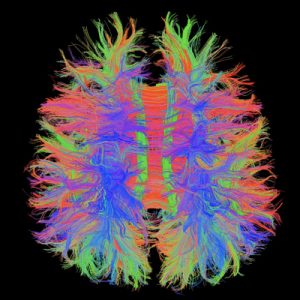

Chẩn đoán toàn thân: đầu, cổ, cột sống, khớp, bụng, tiểu khung, mạch máu

Phù hợp với nghiên cứu và workflow thông minh nhờ kết nối từ xa, các chuỗi quét tiên tiến và xử lý ảnh cao cấp